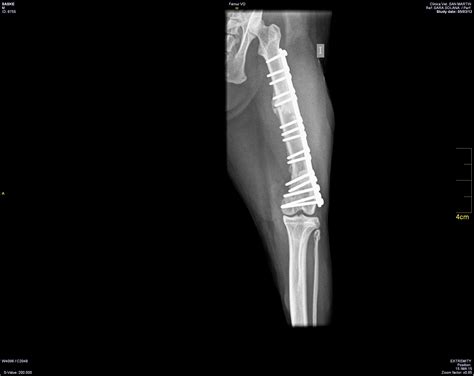

Bone Fracture Xray Image at Jay Hunter blog

Bone Fracture Xray Image at Jay Hunter blog